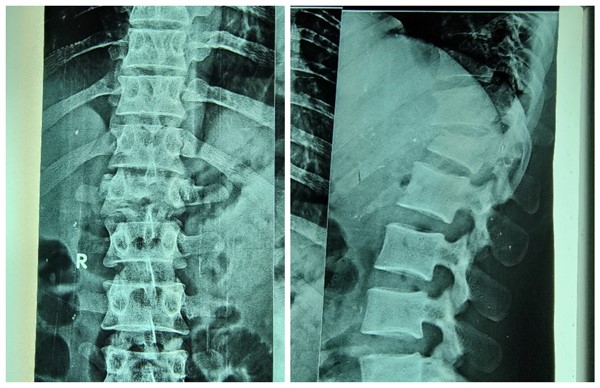

周二一大早,苏丹恩图曼友谊医院骨科门诊就传来了家属急切的声音:“撒艾德 艾黑”(帮帮我的兄弟)。原来是31岁的法拉赫,一月前不慎从高处坠落,当即出现腰痛,双下肢活动受限,大小便失禁。拍片显示腰1压缩骨折。来自援苏丹医疗队骨科的高宗强副主任医师阅片后和家属详细沟通病情,考虑“腰1压缩骨折伴脊髓受压”,当时就建议手术治疗。因患者家庭经济较紧张,患者又行动困难,患者及家属多方商议并考虑再三,再次在骨科门诊当面咨询,高宗强副主任医师耐心细致解答了患者及家属的顾虑,详细讲解了准备实施的手术方案,及可能出现的风险及意外,并与身为骨科大夫的医院院长阿明商议,最大可能的控制手术的费用。病人家属信任的眼神,对手术后康复的急切渴望,这一切都对援苏丹中国医生的肯定。患者入院时,已经是受伤后1月了。入院查体显示,胸腰段有明显叩击痛,左下肢肌力2级,右下肢肌力3级,双侧足背感觉减退,尿管导尿。

“切开,剥离,定位,置钉,减压”,手术过程就像术前预想的那样,术中发现腰1脊髓背侧硬膜囊与黄韧带粘连非常严重,小心翼翼地分离,牵开脊髓,敲击突出骨块,所幸过程相对比较顺利。但因为是脊柱陈旧性骨折,伤椎高度完美恢复难度大,但最重要的减压固定已完成。阿明院长在旁边一直关注着手术的进程,当看到最后一次透视后,他表情放松了,满意地对两位中国医生竖起了大拇指。顺利完成术后,脱掉厚厚的铅衣,周围人才发现两位医生的洗手衣都已被汗水浸透。